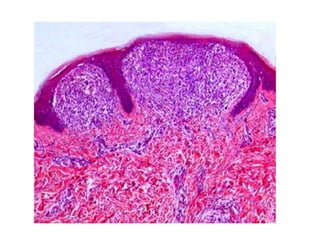

Гистология

• - минимальный лихеноидный лимфоцитарный

инфильтрат,

• - «когтеобразная» конфигурация эпидермиса с

изогнутыми удлиненными гребнями

эпидермиса вокруг лимфоцитарного

инфильтрата сосочковой дермы,

• - может быть паракератоз,

• - воспалительный инфильтрат может

распространяться на эпидермис.